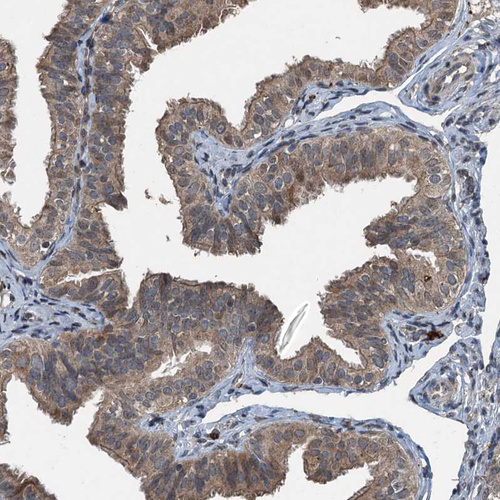

Immunohistochemical staining of human fallopian tube shows moderate cytoplasmic positivity in glandular cells.